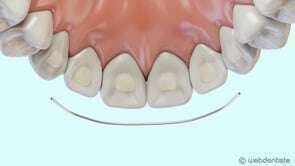

Fil de contention